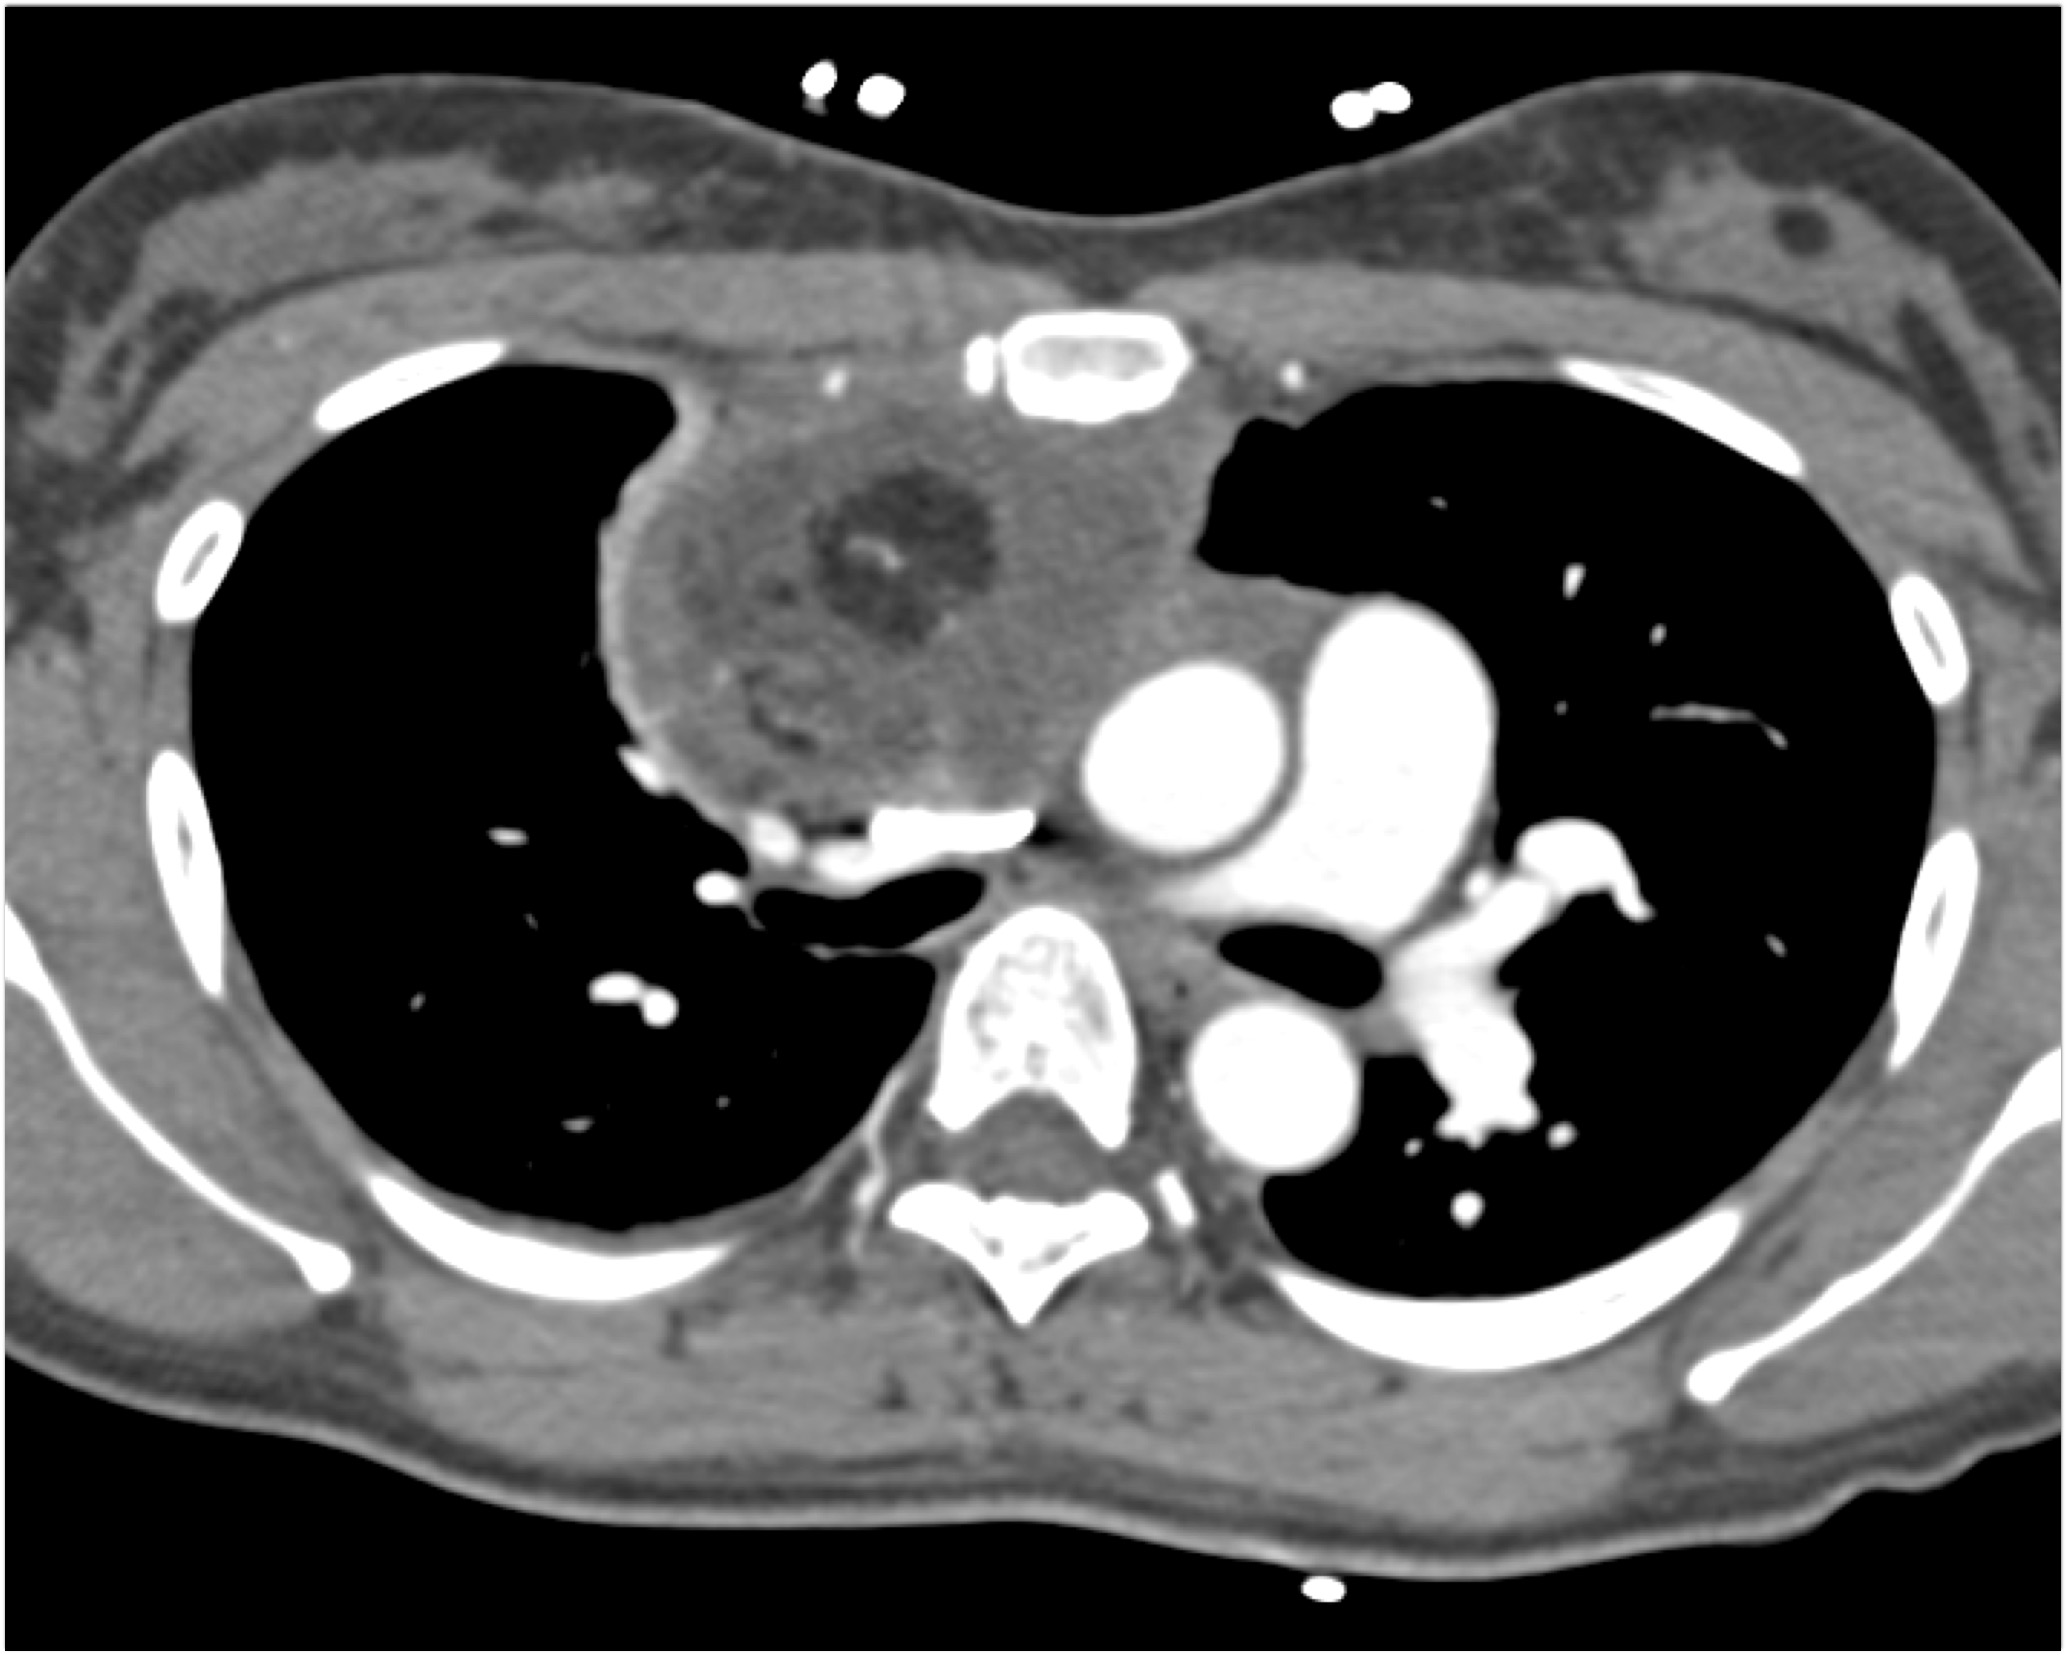

- Evaluate the CT images of each question carefully.